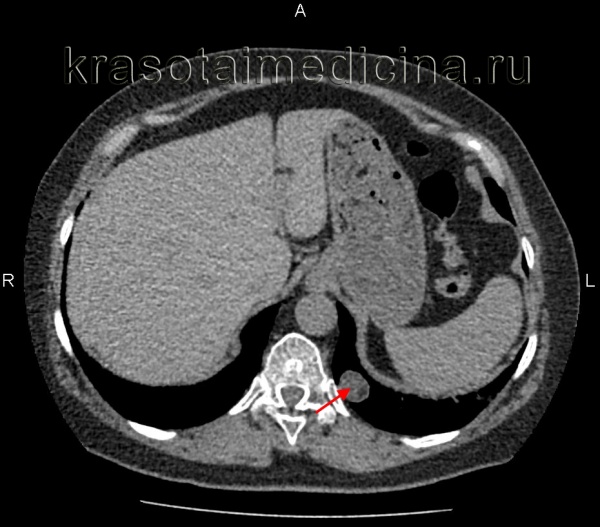

(Слева) МРТ, Т1 -ВИ, сагиттальный срез: у ребенка с преждевременным половым созреванием определяется крупное дольчатое супраселлярное объемное образование, изоинтенсивное по отношению к коре и отчетливо не связанное с гипофизом и зрительным перекрестом. Это образование имеет настолько крупные размеры, что смещает ствол мозга кзади.

(Справа) МРТ, Т2-ВИ, аксиальный срез: у этого же пациента отмечается неоднородно гиперинтенсивное по отношению к коре объемное образование. Гамартома гипоталамуса (ГГ) может достигать нескольких сантиметров в диаметре. Это образование было удалено, оно состояло из дисплазированного и дезорганизованного серого вещества и соответствовало гамартоме гипоталамуса (ГГ).